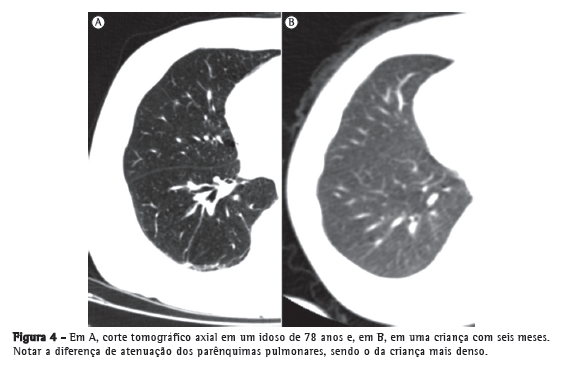

Turner et al.(34) relataram que, em indivíduos com idades entre 20 e 60 anos, a relação do peso do pulmão com o peso corporal não diminui com o envelhecimento, o que sugere ou pouca/nenhuma destruição do pulmão ou a substituição de tecidos.(34,36,37) Durante o curso do envelhecimento, os ductos alveolares aumentam seu diâmetro, e os alvéolos tornam-se mais largos e rasos. Após a quarta década de vida, uma parte das fibras elásticas dos bronquíolos respiratórios e alvéolos degenera, o que diminui sua complacência.(38) Tais mudanças são mais marcantes ao redor dos ductos alveolares. Consequentemente, ocorre a dilatação desses ductos, seguida pelo alargamento dos espaços aéreos.(32) Esse alargamento é notavelmente homogêneo, ao contrário da distribuição irregular de alargamento do espaço aéreo no enfisema (Figuras 3 e 4).

No estudo por TC do parênquima pulmonar, identificam-se alguns achados radiológicos muito comuns em idosos, e especula-se que eles tenham relação com as alterações do colágeno. Esses achados são atelectasias laminares, na maioria das vezes posteriores e basais, localizadas em áreas pendentes dos pulmões (Figura 5); espessamentos lineares subpleurais (Figura 6); áreas de aprisionamento aéreo (Figura 7); espessamento e ectasia brônquica (Figura 8); e cistos pulmonares.(41,50-53)